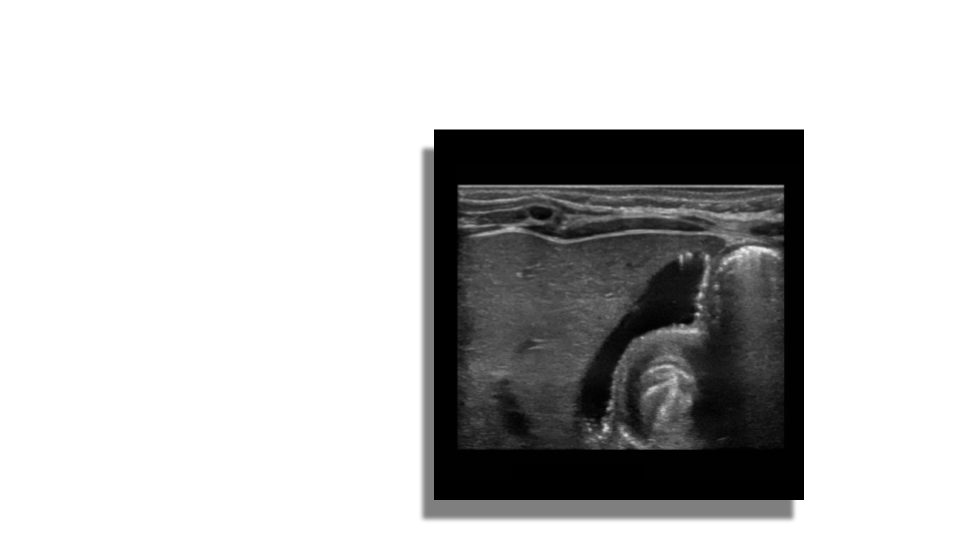

Adenomyomatosis

Adenomyomatosis is a benign condition in the epithelium of the GB wall. There is overgrowth of the mucosa, thickening of the muscular wall and formation of intramural diverticula known as Rokitansky-Aschoff sinuses. Within these cystic spaces biliary crystals can get trapped given the sonographic appearance of echogenic foci with comet tail artifacts posteriorly. The changes can be focal or diffuse.